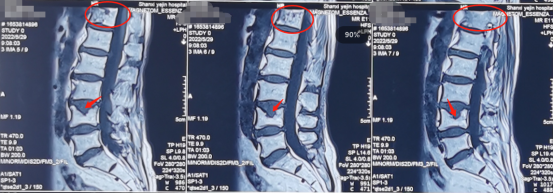

熊东主任接诊后,根据李奶奶的X线片以及核磁共振片子,发现她出现了胸12椎体压缩性骨折,并有轻度楔形变;腰4椎体陈旧骨折伴上缘许莫氏结节。而导致李奶奶的莫名腰背痛的原因正是脊柱的压缩性骨折。

术前影像学检查: